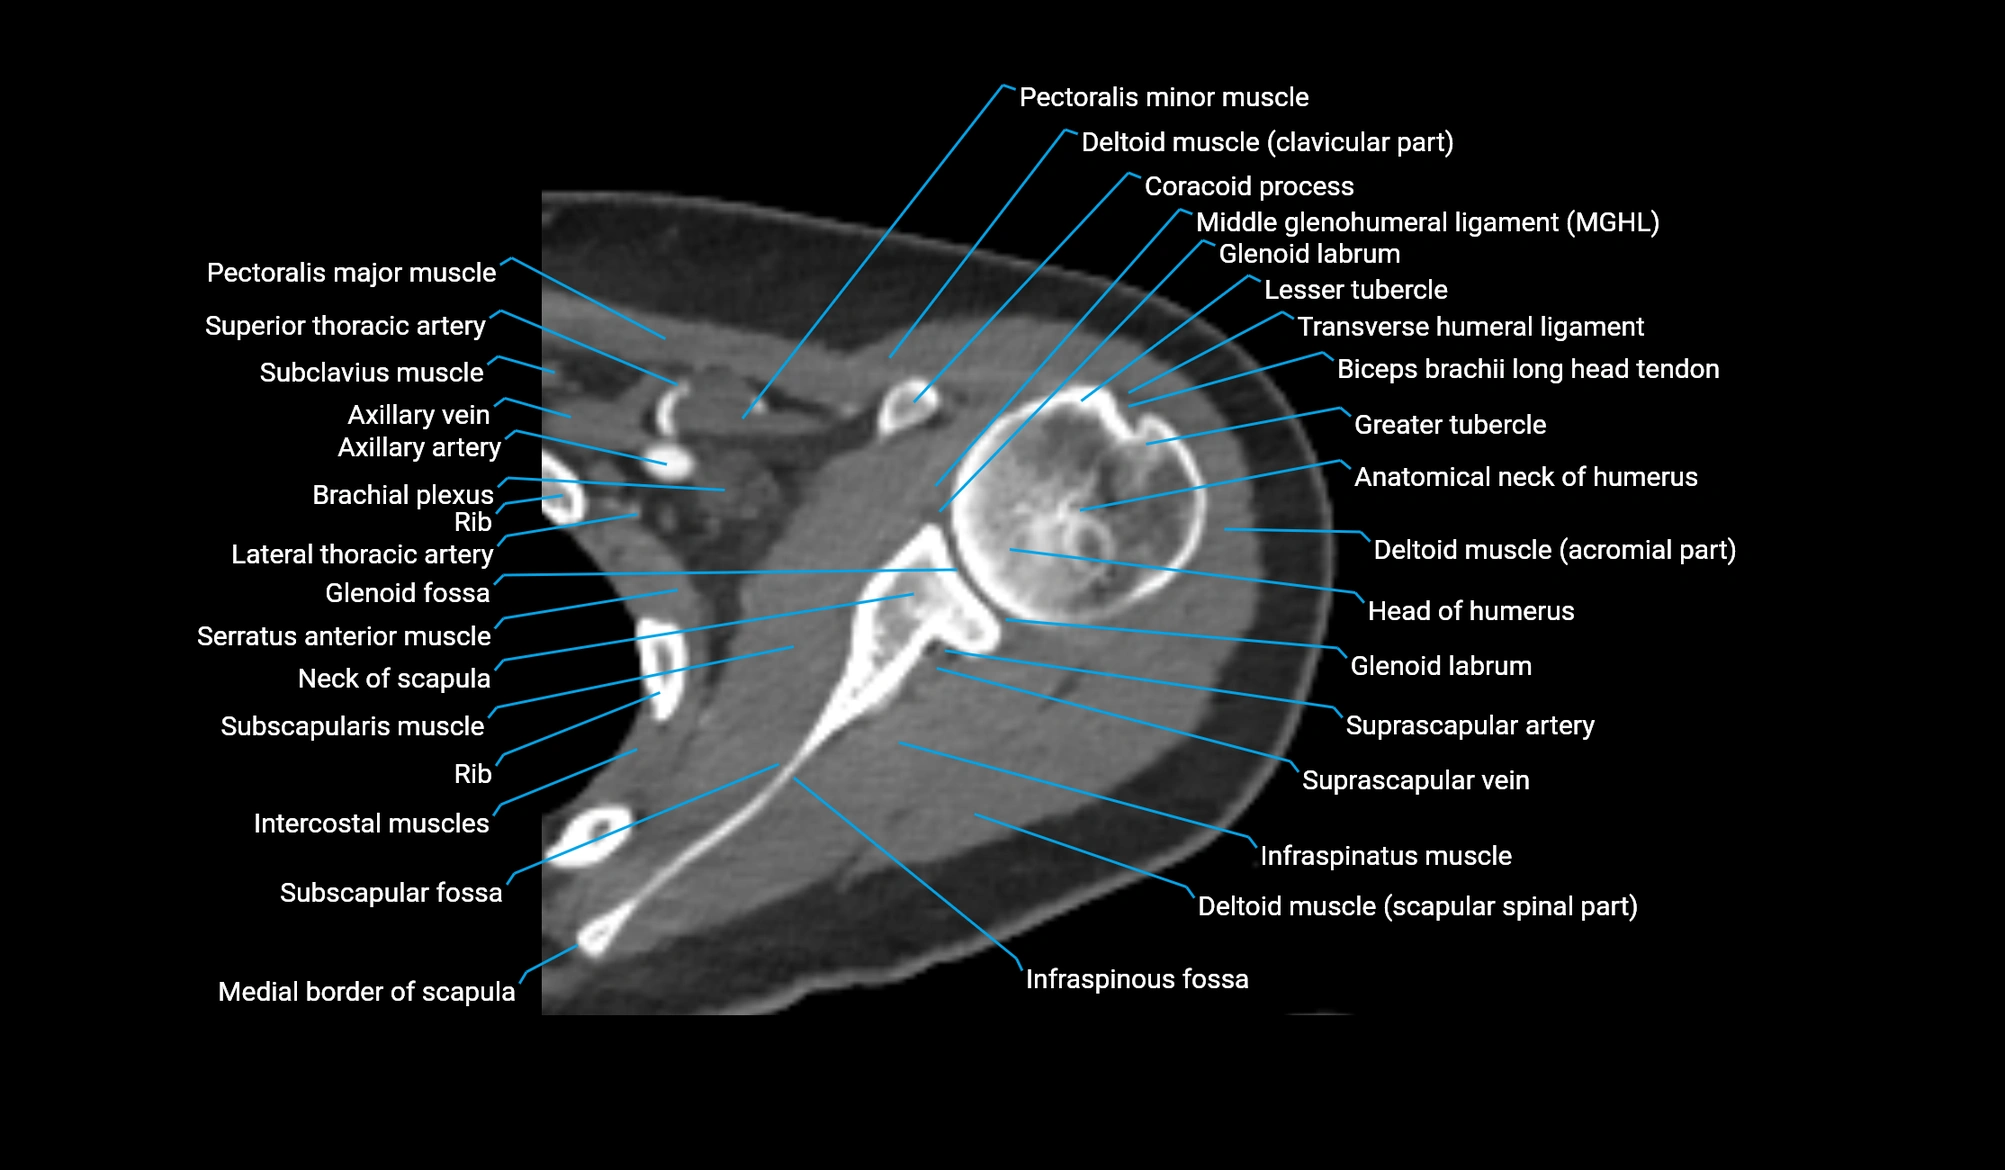

- Head of humerus

- Glenoid labrum

- Glenoid fossa

- Greater tubercle of humerus

- Lesser tubercle of humerus

- Subscapularis muscle

- Infraspinatus muscle

- Infraspinous fossa

- Subscapular fossa

- Brachial plexus

- Pectoralis major muscle

- Pectoralis minor muscle

- Subclavius muscle

- Coracoid process of scapula

- Middle glenohumeral ligament